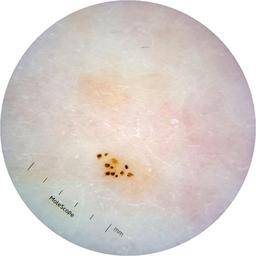

ISIC_6363669

Information

923 x 923

Clinical

Field Value

acquisition_day 264

age_approx 65

anatom_site_1 Trunk

anatom_site_2 Anterior trunk

anatom_site_general anterior torso

concomitant_biopsy False

diagnosis_1 Benign

diagnosis_confirm_type single image expert consensus

family_hx_mm True

image_manipulation instrument only

image_type dermoscopic

lesion_id IL_2591344

patient_id IP_1322385

personal_hx_mm True

sex female